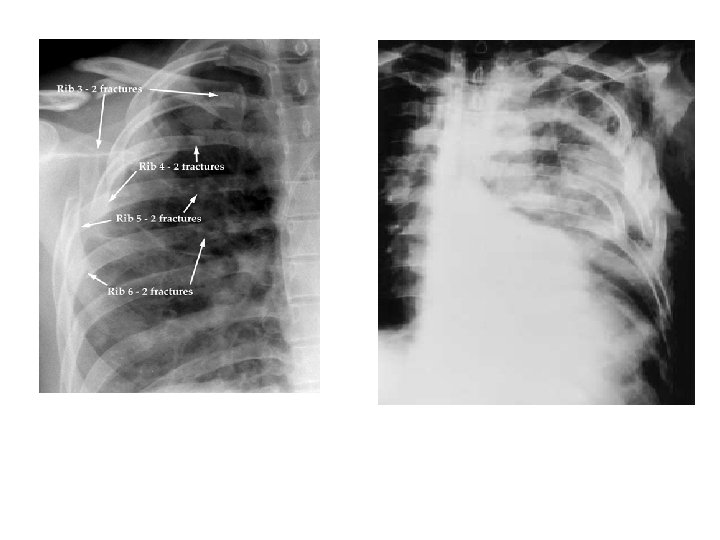

3) YELKEN GÖĞÜS • İki yada daha fazla komşu kostanın, iki veya daha fazla yerinden kırılması • Segment altındaki akciğer bölgesindeki yaralanma belirgin ve ciddi hipoksi • Alttaki pulmoner kontüzyon majör zorluk • Eşlik eden ağrı ve altta yatan akciğer yaralanması hipoksiye katkıda bulunur.

Solunum hareketleri zayıf, Toraks hareketi asimetrik ve unkoordine X-ray, AKG Başlangıç tedavisi, – yeterli ventilasyon, – nemli o 2 uygulanması – sıvı replasmanı (aşırı sıvı yüklemesine dikkat) – analjezi. • Solunum sayısı, PO 2, solunum çabası entübasyon kararı? • •

İKİNCİL BAKI • Daha derin fizik muayene • Akciğer filmi, AKG, pulse oksimetre ve EKG’ye bakılır. • Multiple kosta kırığı ve 1. ve/veya 2. kostanın kırılmış olması göğüs duvarı ve derin dokularını şiddetli bir travmaya maruz kaldığını düşündürür.

C. KOSTA, STERNUM VE SKAPULAR KIRIKLAR � Skapula, 1. - 2. kosta veya sternum kırıkları baş, boyun, spinal kord, akciğer ve büyük damar yaralanmaları (mort % 35) � Sternal kırıklarla birlikte pulmoner kontüzyon ve kardiak yaralanma � Genç hastalar � Lokalize ağrı, palpasyonda gerginlik ve krepitasyon kosta yaralanması � Kostakondral ayrılmalar X-ray ile görüntülenemez. � Yeterli ventilasyon için analjezi